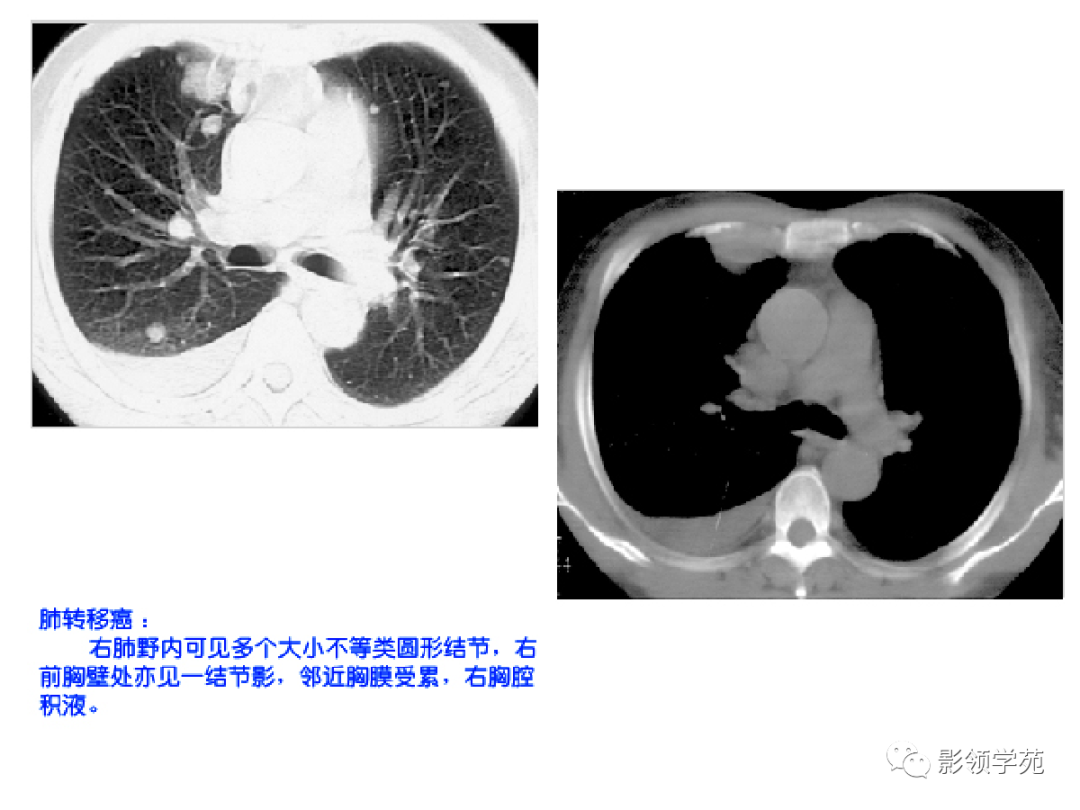

1. 血行性转移 :多发或单发结节,大小不一,边缘较清楚。少数结节伴出血时出现晕轮征,即有略高密度影像环绕结节,使病变边缘模糊。病变有钙化常见于骨肉瘤或软骨肉瘤转移。转移瘤亦可表现为空洞。两肺多发的小结节影具有随机分布的特点,HRCT显示结节位于小叶中心、小叶间隔、支气管血管束及胸膜,结节大小不均匀。

肺转移瘤。

肺窗像(A)示双肺野可见大小不等的圆形高密度结节影,纵隔增宽;纵隔窗像(B)示肺内肿块呈实性,纵隔满布大小不等的肿大淋巴结